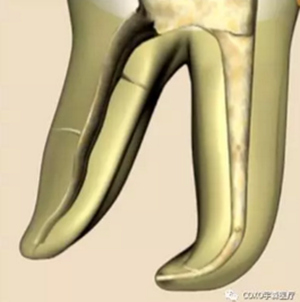

( 1 )直線通路:根管治療時需要一個直線通路,直線通路能夠達(dá)到根尖三分之一

測量標(biāo)準(zhǔn):以允許根管器械直線并直接進(jìn)入根尖 1/3 且不接觸冠方各壁為標(biāo)準(zhǔn)。

( 2 )髓腔其他改變:如髓室頂、繼發(fā)性牙本質(zhì)、修復(fù)性或增齡性牙本質(zhì)。見左圖。

右圖中有繼發(fā)性牙本質(zhì),切削后獲得直線通路。